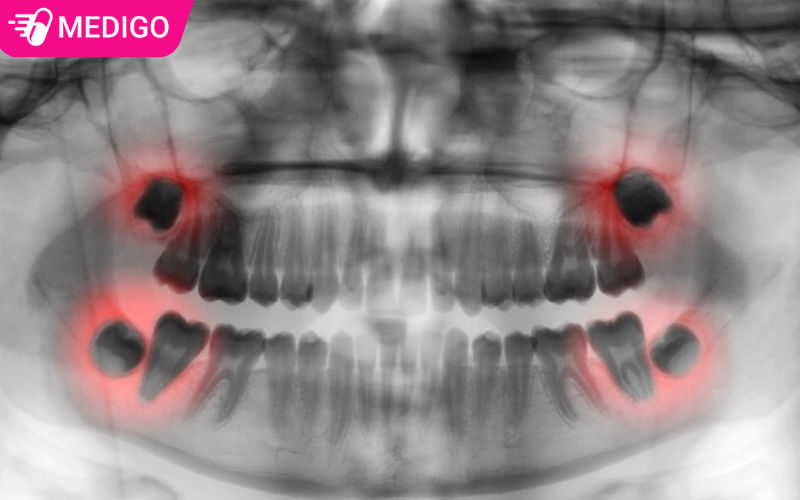

Răng khôn (hay còn gọi là răng số 8) là chiếc răng hàm cuối cùng mọc ở mỗi bên hàm. Đa số người trưởng thành có 4 chiếc răng khôn, nằm ở 4 góc trong cùng của miệng. Vì mọc sau cùng và ở độ tuổi đã trưởng thành, nên chúng được gọi là “răng khôn”.

Bước vào độ tuổi từ 18 đến 25, khi khung xương hàm đã định hình ổn định và trở nên cứng cáp, răng khôn mới bắt đầu hành trình mọc lên. Chính vì vậy, chúng thường rơi vào tình trạng thiếu khoảng trống, dẫn đến việc không thể mọc ngay ngắn như các răng khác. Đồng thời, nướu và mô mềm phủ trên xương ở vị trí răng khôn thường dày và chắc, làm răng khó trồi lên, dẫn đến tình trạng mọc lệch hoặc mọc ngầm.

Trước hết, nên khám nha khoa định kỳ 6 tháng/lần để bác sĩ kiểm tra sự phát triển của răng khôn và sớm phát hiện các dấu hiệu mọc lệch. Việc chụp X-quang răng khôn giúp đánh giá vị trí và hướng mọc, từ đó có kế hoạch theo dõi hoặc can thiệp kịp thời. Cần vệ sinh răng miệng kỹ lưỡng, duy trì thói quen ăn uống lành mạnh, tránh chỉ ăn thức ăn quá mềm trong thời gian dài, cũng góp phần hỗ trợ sức khỏe răng hàm.